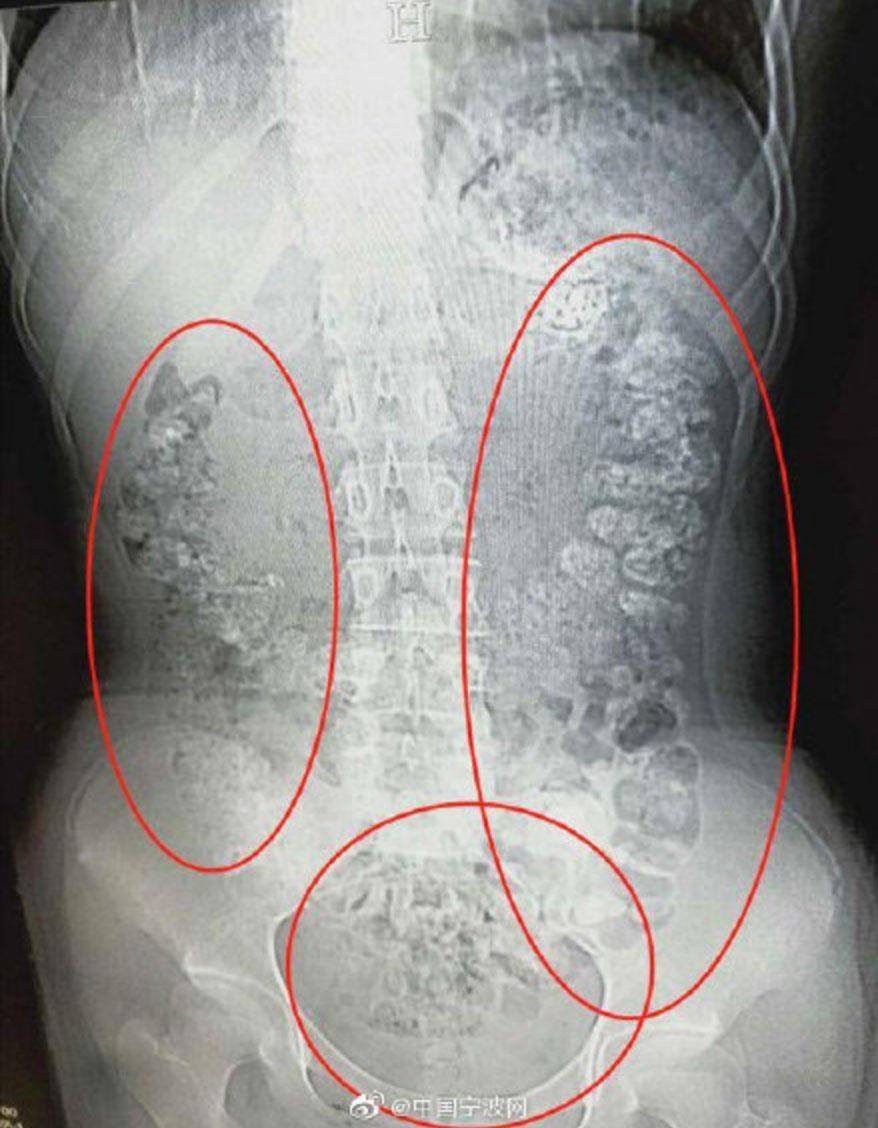

Sau khi chụp X-quang, các bác sĩ nhìn thấy một khối đen gồm những viên nhỏ dạng hình tròn. Họ cho biết, đó là lượng trân châu chưa được tiêu hóa từ những cốc trà sữa mà nữ sinh này đã uống từ nhiều ngày trước.

| Ảnh chụp X-quang cho thấy có hàng trăm viên trân châu nằm trong bụng bé gái. Ảnh: Sina. |